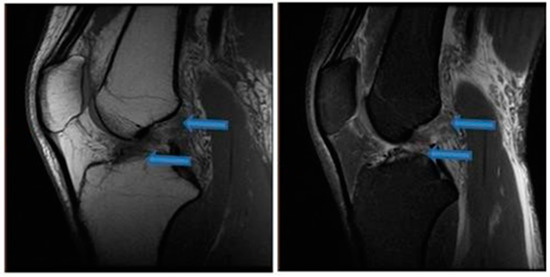

| 24 December 2021 | MRI scans confirming signs of complete ACL, MCL and medial meniscus healing |